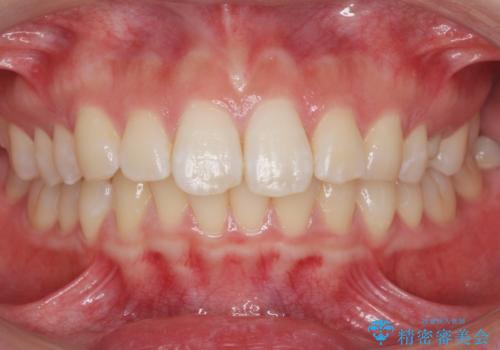

自然な仕上がりにご満足頂けました。

「うわー、自分の歯みたい!すごい!」と喜んで下さいました。

ホワイトニングも行い、口元の印象が明るくなりました。